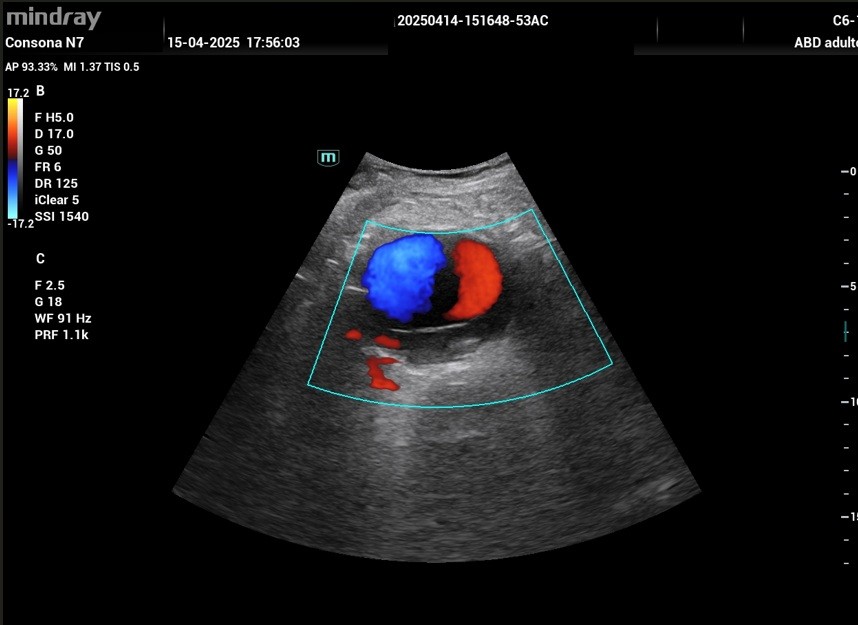

En el plano transversal se objetiva la dilatación de la aorta de hasta 5,91 cm de diámetro total, con presencia de trombo mural en pared posterior que deja una luz respetada de un diámetro de 4,19 cm (Imagen 2). Con Doppler Color se visualiza el signo del Yin -Yang, que representa un flujo anterógrado y retrógrado que puede aparecer en aneurismas y pseudoaneurismas. (Imagen 3).